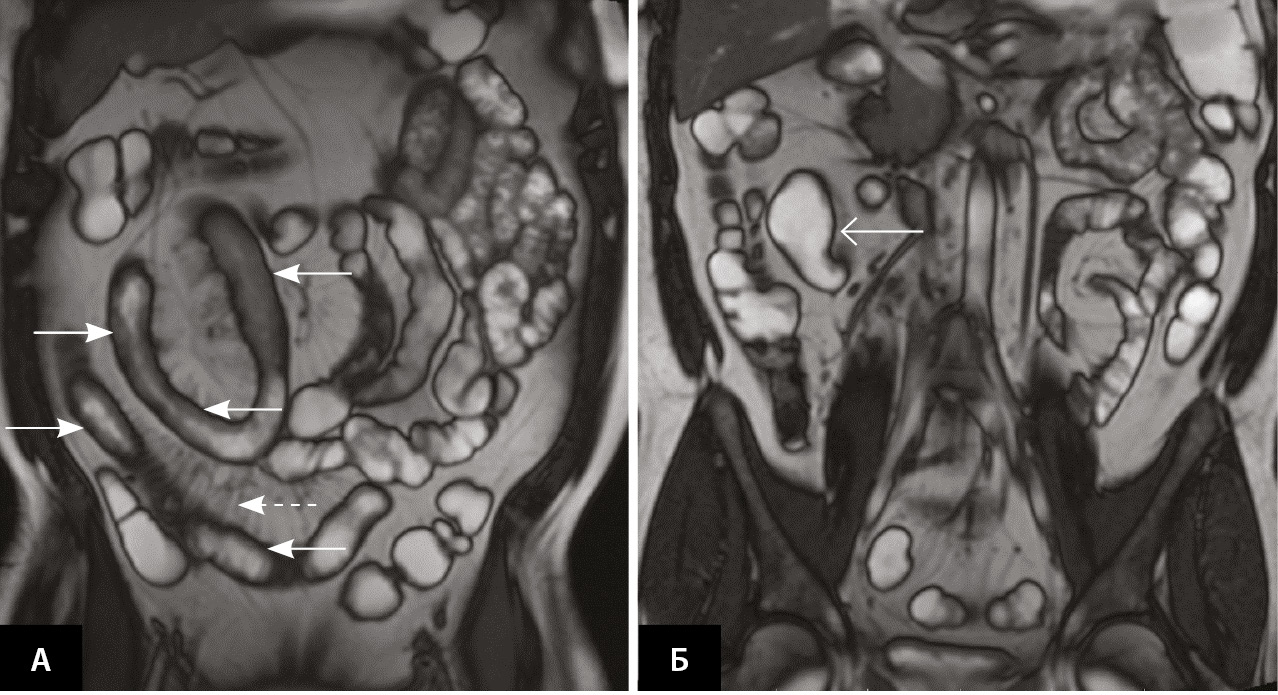

Осенью 2019 г. (в возрасте 39 лет) пациент обратился в кабинет воспалительных заболеваний кишечника (ВЗК) ФГБОУ ВО «Первый Санкт-Петербургский государственный медицинский университет имени академика им. И. П. Павлова» Минздрава России. При лабораторном обследовании выявлено повышение скорости оседания эритроцитов до 62 мм/ч (норма (N) – 2–15 мм/ч), С-реактивного белка (СРБ) до 63,01 мг/л (N ≤ 5 мг/л), фекального кальпротектина (ФК) до 1039 мкг/г (N ≤ 50 мкг/г). Результат ЭГДС: по большой кривизне тела желудка язвенный дефект 0,7 × 0,5 см, дно язвы под фибрином с налетом гематина, край умеренно приподнятый. Гистологическое исследование биоптата слизистой оболочки желудка: эпителизирующаяся острая эрозия фундального отдела желудка, хронический фундальный гастрит со слабым воспалительным компонентом, минимальной активностью, обсеменения Helicobacter pylori не выявлено. При ИКС наблюдалось сужение подвздошной кишки (на 5 см дистальнее баугиниевой заслонки), непроходимое для эндоскопа диаметром 12 мм, отек и гиперемия слизистой оболочки терминального отдела подвздошной кишки с утолщенными ворсинами и множественными сливными афтозно-язвенными дефектами под фибрином, а также деформация илеоцекального клапана с формированием на поверхности плоских язвенных дефектов до 1,0–1,5 см (9 баллов по SES-CD (англ. Simple Endoscopic Score for Crohn’s Disease – Простая эндоскопическая шкала БК)). При гистологическом исследовании обнаружен хронический сегментарный эрозивно-язвенный илеит с фокально выраженным воспалительным компонентом и высокой активностью, толстокишечной метаплазией эпителия; хронический сегментарный эрозивно-язвенный баугинит с фокально выраженным воспалительным компонентом и высокой активностью, распространенной воспалительной инфильтрацией в подслизистом слое, без признаков гранулематозного компонента; поверхностный колит с минимальным воспалительным компонентом, без активности. По данным магнитно-резонансной энтерографии выявлены признаки стриктурирующей формы БК умеренной активности (по классификации J. Panes) с поражением дистальных петель и терминального отдела подвздошной кишки (рис. 1).

Рис. 1. Магнитно-резонансная энтерография (01.10.2019), Т1-взвешенное изображение после внутривенного контрастного усиления (гадобутрол, 5 мл), фронтальная проекция: A – асимметричное утолщение стенки в дистальных петлях подвздошной кишки и терминальном отделе подвздошной кишки (сплошные стрелки), незначительно выраженная сосудистая реакция брыжейки (пунктирная стрелка); Б – престенотическое расширение подвздошной кишки перед местом поражения (открытая стрелка)